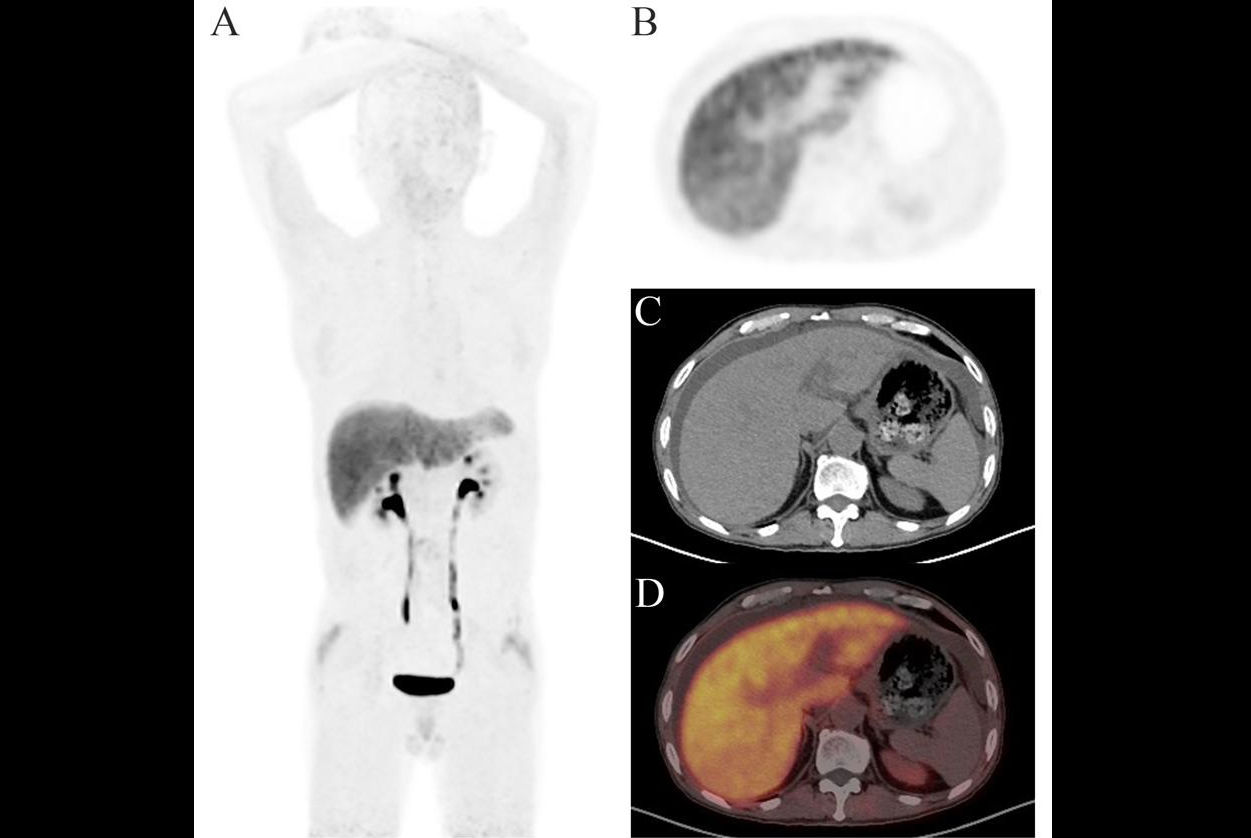

Effect of serum ketone level on cerebral SUVbw. Sample images of two patients thresholded identically with the same blood glucose level, but different serum ketone levels illustrate the reduction in FDG uptake in the brain seen with a higher serum ketone level. Image courtesy of the European Journal of Hybrid Imaging through CC BY 4.0 International License.As they expected, the researchers found a negative association between serum glucose levels and whole-brain F-18 FDG uptake. However, they also noted a reduction in SUVbw due to increasing serum ketones levels that were independent of and in addition to the effects of glucose.